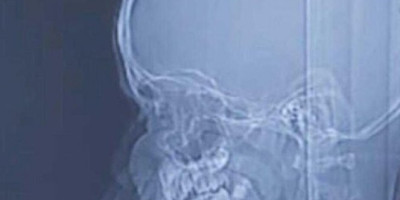

Odmah su ga pregledali, a na glavi su mu pronašli malenu ranu i krv na vlasištu. Odmah su mu napravili CT nakon čega su otkrili kako dečak ima metak u glavi. Metak je prošao kroz lobanju i zaustavio se u dečakovu mozgu.

Neurohirurg Gaj Elor, koji je izvadio metak iz dečakove glave, kaže da roditelji nisu znali da je njihov sin pogođen.

Foto: Hadassah university hospital

– Majka je rekla da se igrao sa svojim prijateljima i da se nešto dogodilo, da je možda palo nešto na njega. Priča nije potpuno jasna. Imao je malenu ranu na glavi – rekao je lekar, piše Tajms of Izrael.

Sumnja se da je dečak pogođen tokom proslave Kurban-bajrama.

– Da je metak otišao u drugom smeru, mogao je da prouzrokuje mnogo veću štetu i značajno neurološko oštećenje – rekao je lekar i dodao da se dečak dobro oporavlja i razgovara sa svojom porodicom.